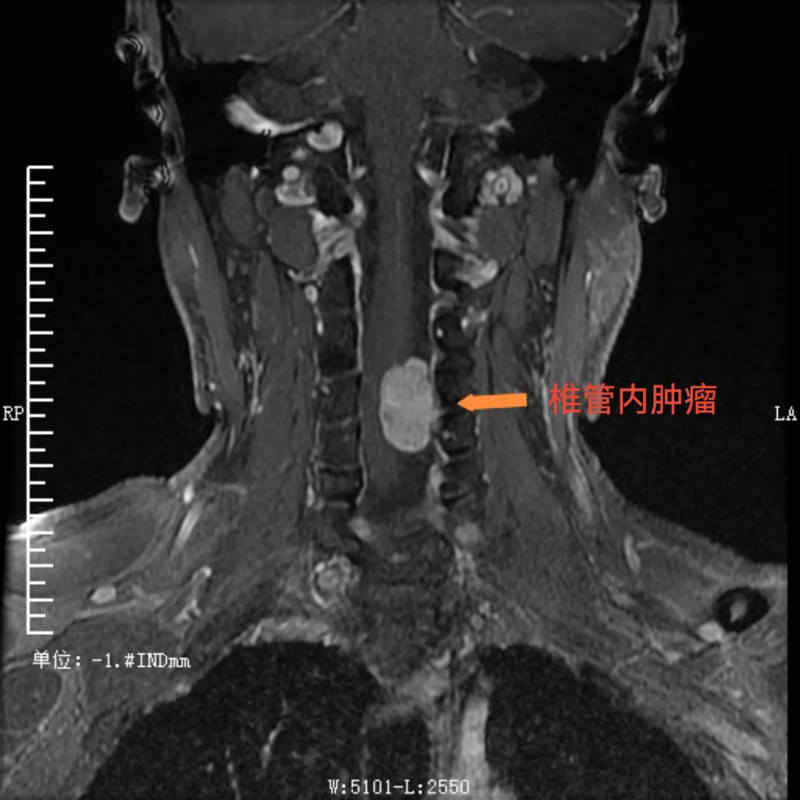

患者潘某(化名),是一位38岁的男性,一直被“左上肢感觉异常、乏力”的症状困扰8个多月。起初,他在贵州荔波县当地医院进行诊治,后根据患者意愿,转到河池市三医院神经外科接受进一步诊疗,到院后,经检查,明确了他的病因:原来是颈椎4-5节段椎管内长了肿瘤。这一肿瘤的存在严重影响了他的神经功能,导致了上肢的不适症状。对于患者来说,这无疑是一个沉重的打击。

术前,可见椎管内肿瘤